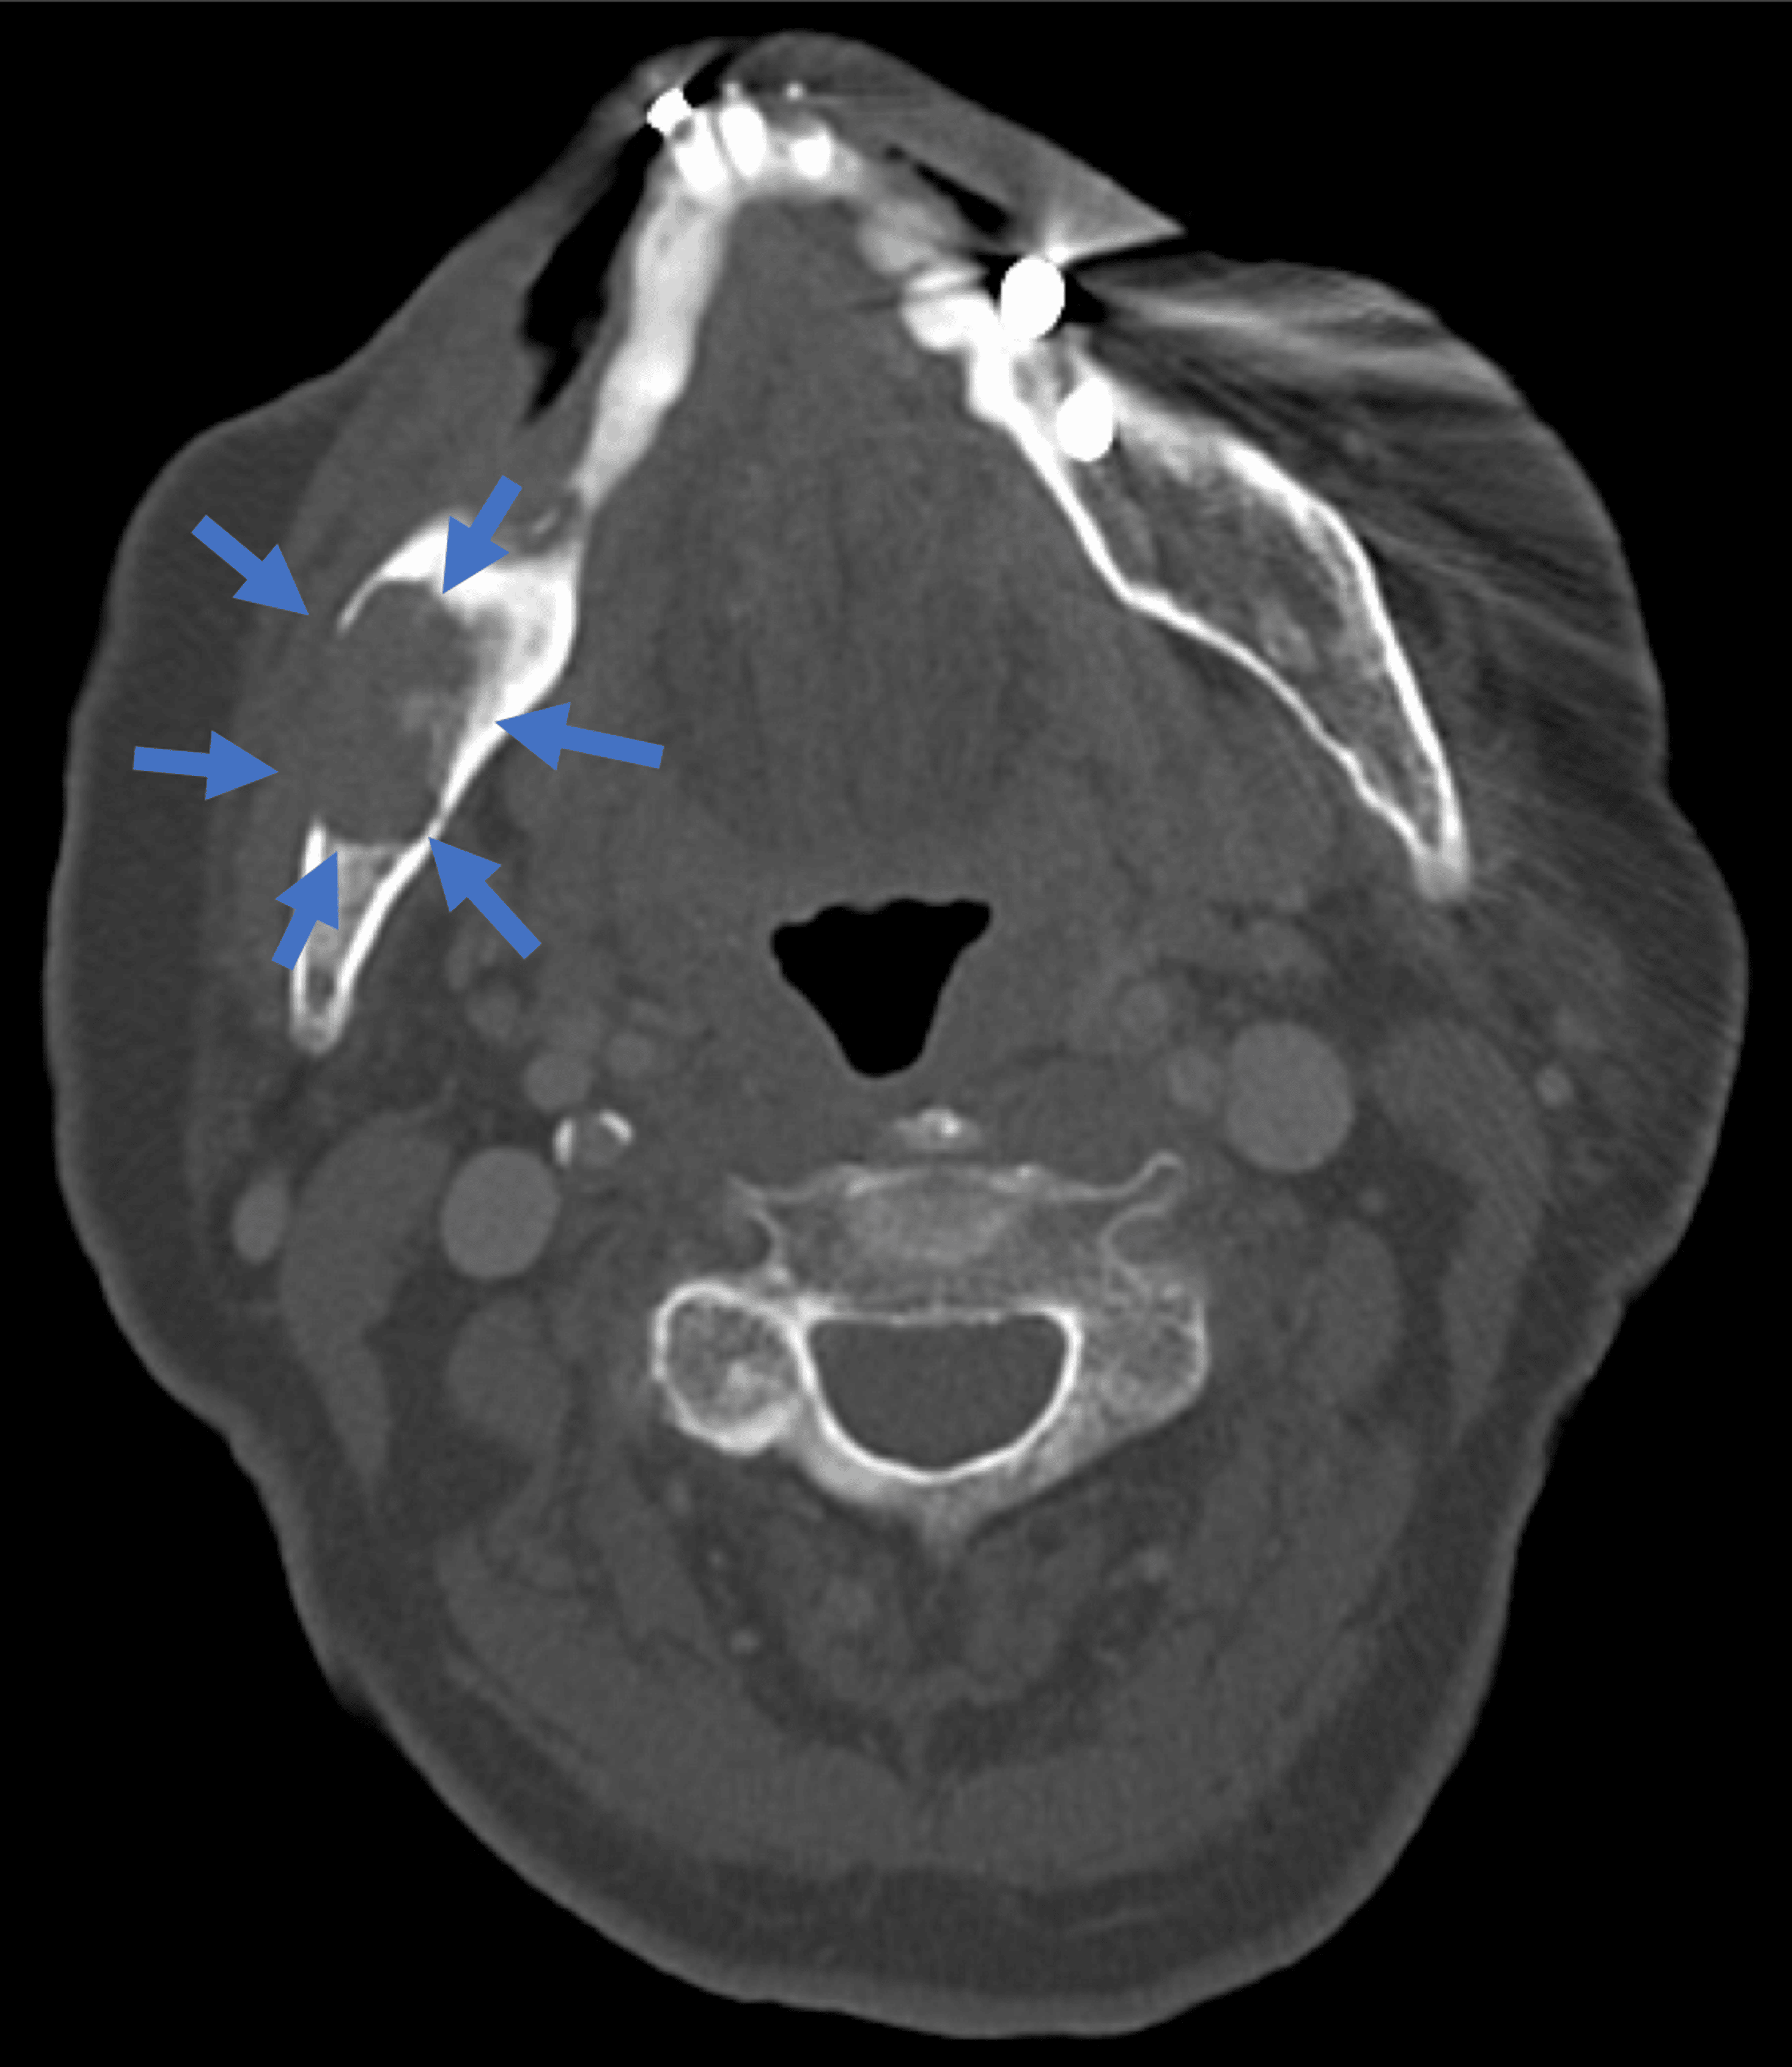

Spindle cell in a 64 years old male patient. Axial CT images... Download Scientific Spindle-Cell Sarcoma Jaw This diagnosis includes fibrosarcoma and sarcomas with indeterminate histomorphology, excluding melanocytic tumors and sarcomas that can be differentiated by histomorphology. Spindle cell carcinoma (scc) is a rare variant of squamous cell carcinoma characterized by elongated and pleomorphic. Spindle cell sarcoma (scs) is a malignancy, with the most recent surveillance, epidemiology, and end results (seer) data citing a total of 250. Spindle-Cell Sarcoma Jaw.